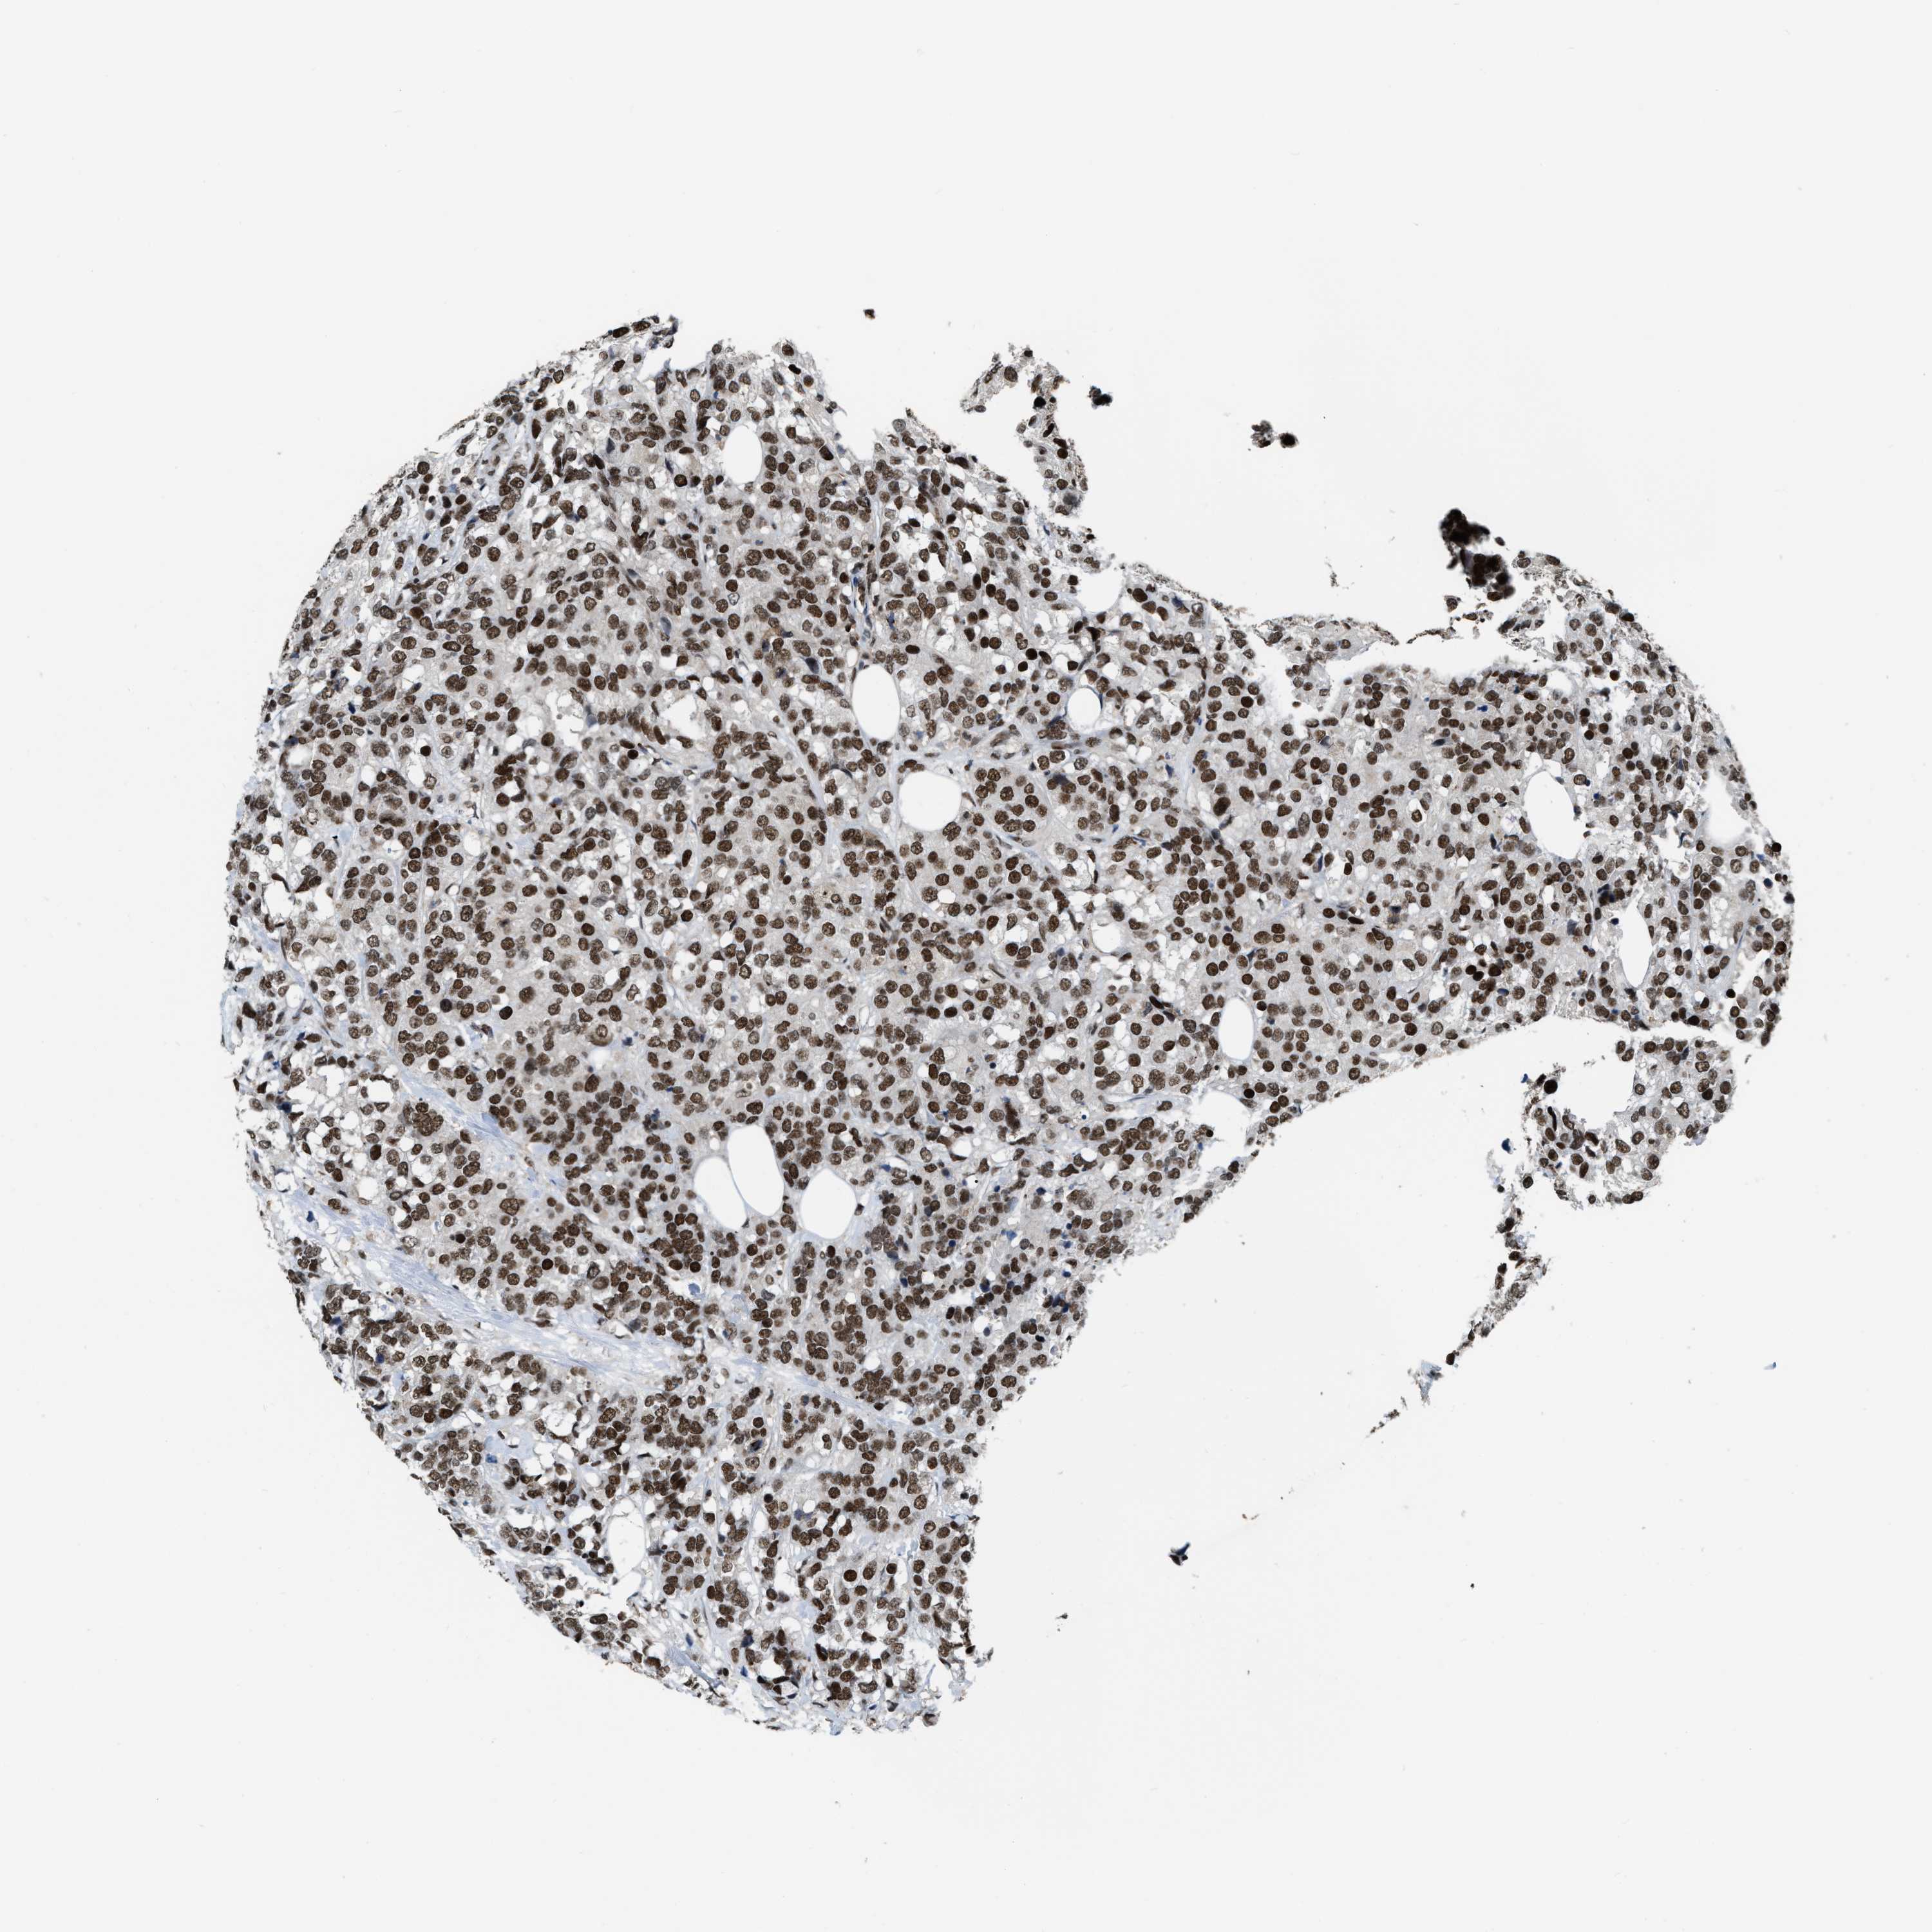

CANCER BREAST CANCER Show tissue menu

BRCA TCGA BRCA VALIDATION PROTEIN EXPRESSION

Breast cancer

Human cancer

Breast invasive carcinoma